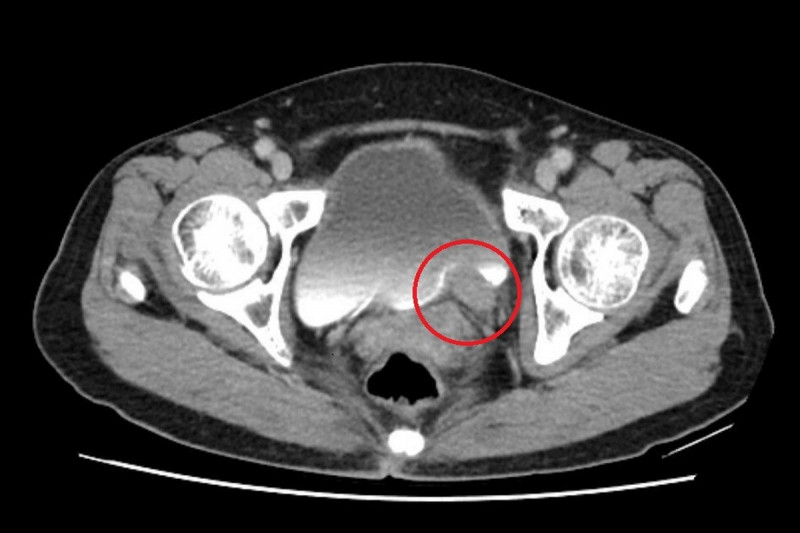

〔記者翁聿煌/新北報導〕67歲林女士近期出現間歇性無痛血尿,原本以為只是小問題,至醫院檢查後,竟發現左側輸尿管末端長了一顆5公分腫瘤,並造成腎水腫情形,確診為輸尿管泌尿上皮癌後,醫師安排化療縮小腫瘤,再利用達文西手術(需自費)切除腫瘤並重建輸尿管,成功保留腎臟功能,林女士術後追蹤至今,病情控制良好。

台北慈濟醫院泌尿科醫師許竣凱指出,根據衛生福利部統計,泌尿上皮癌發生率每10萬人中約有40至50例,臨床上,醫師會以尿液檢驗、膀胱鏡、超音波與電腦斷層進行診斷,排除泌尿道感染、輸尿管結石等會伴隨疼痛的血尿後,就要高度懷疑腫瘤的可能。